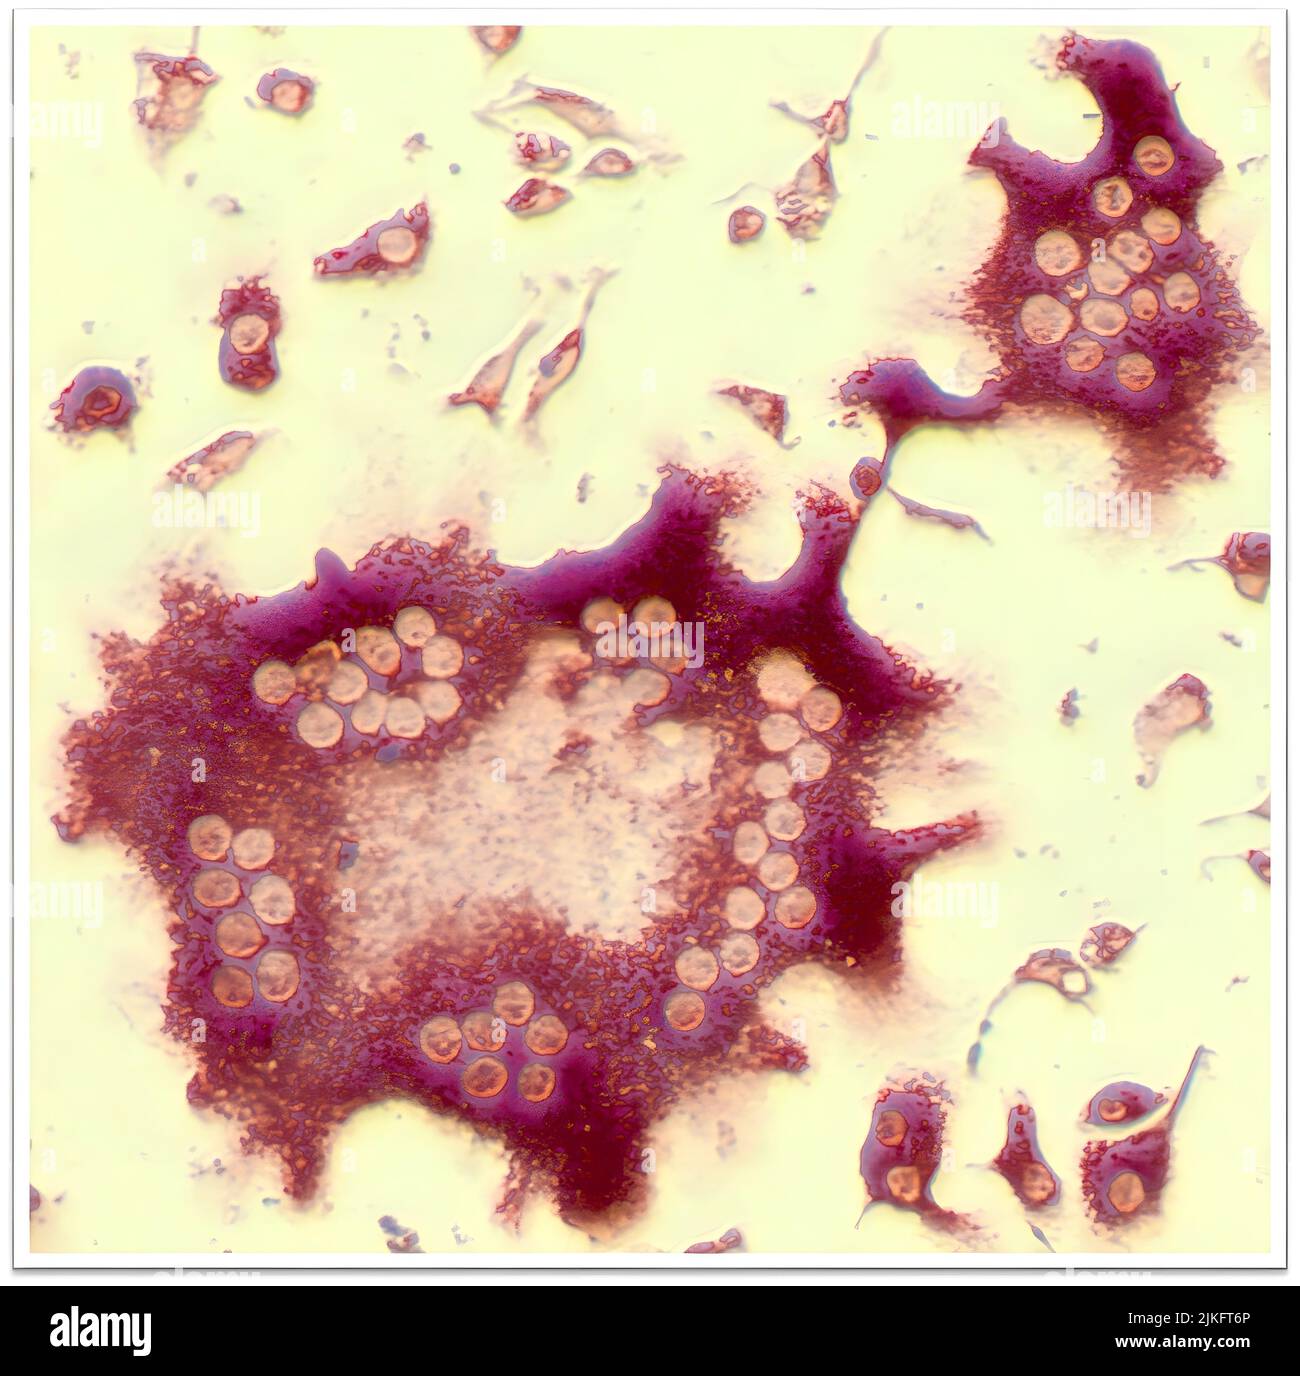

RM2JKFT6P–Gli scienziati NIAMS hanno trovato la prova che un elevato numero di osteoclasti, un tipo di cellula che si rompe l'osso, può contribuire alla perdita dell'osso in persone con spondiloartrite. Gli osteoclasti, come quello mostrato qui al centro, contengono nuclei multipli (cerchi leggeri) perché sono formati per fusione di cellule precursori.